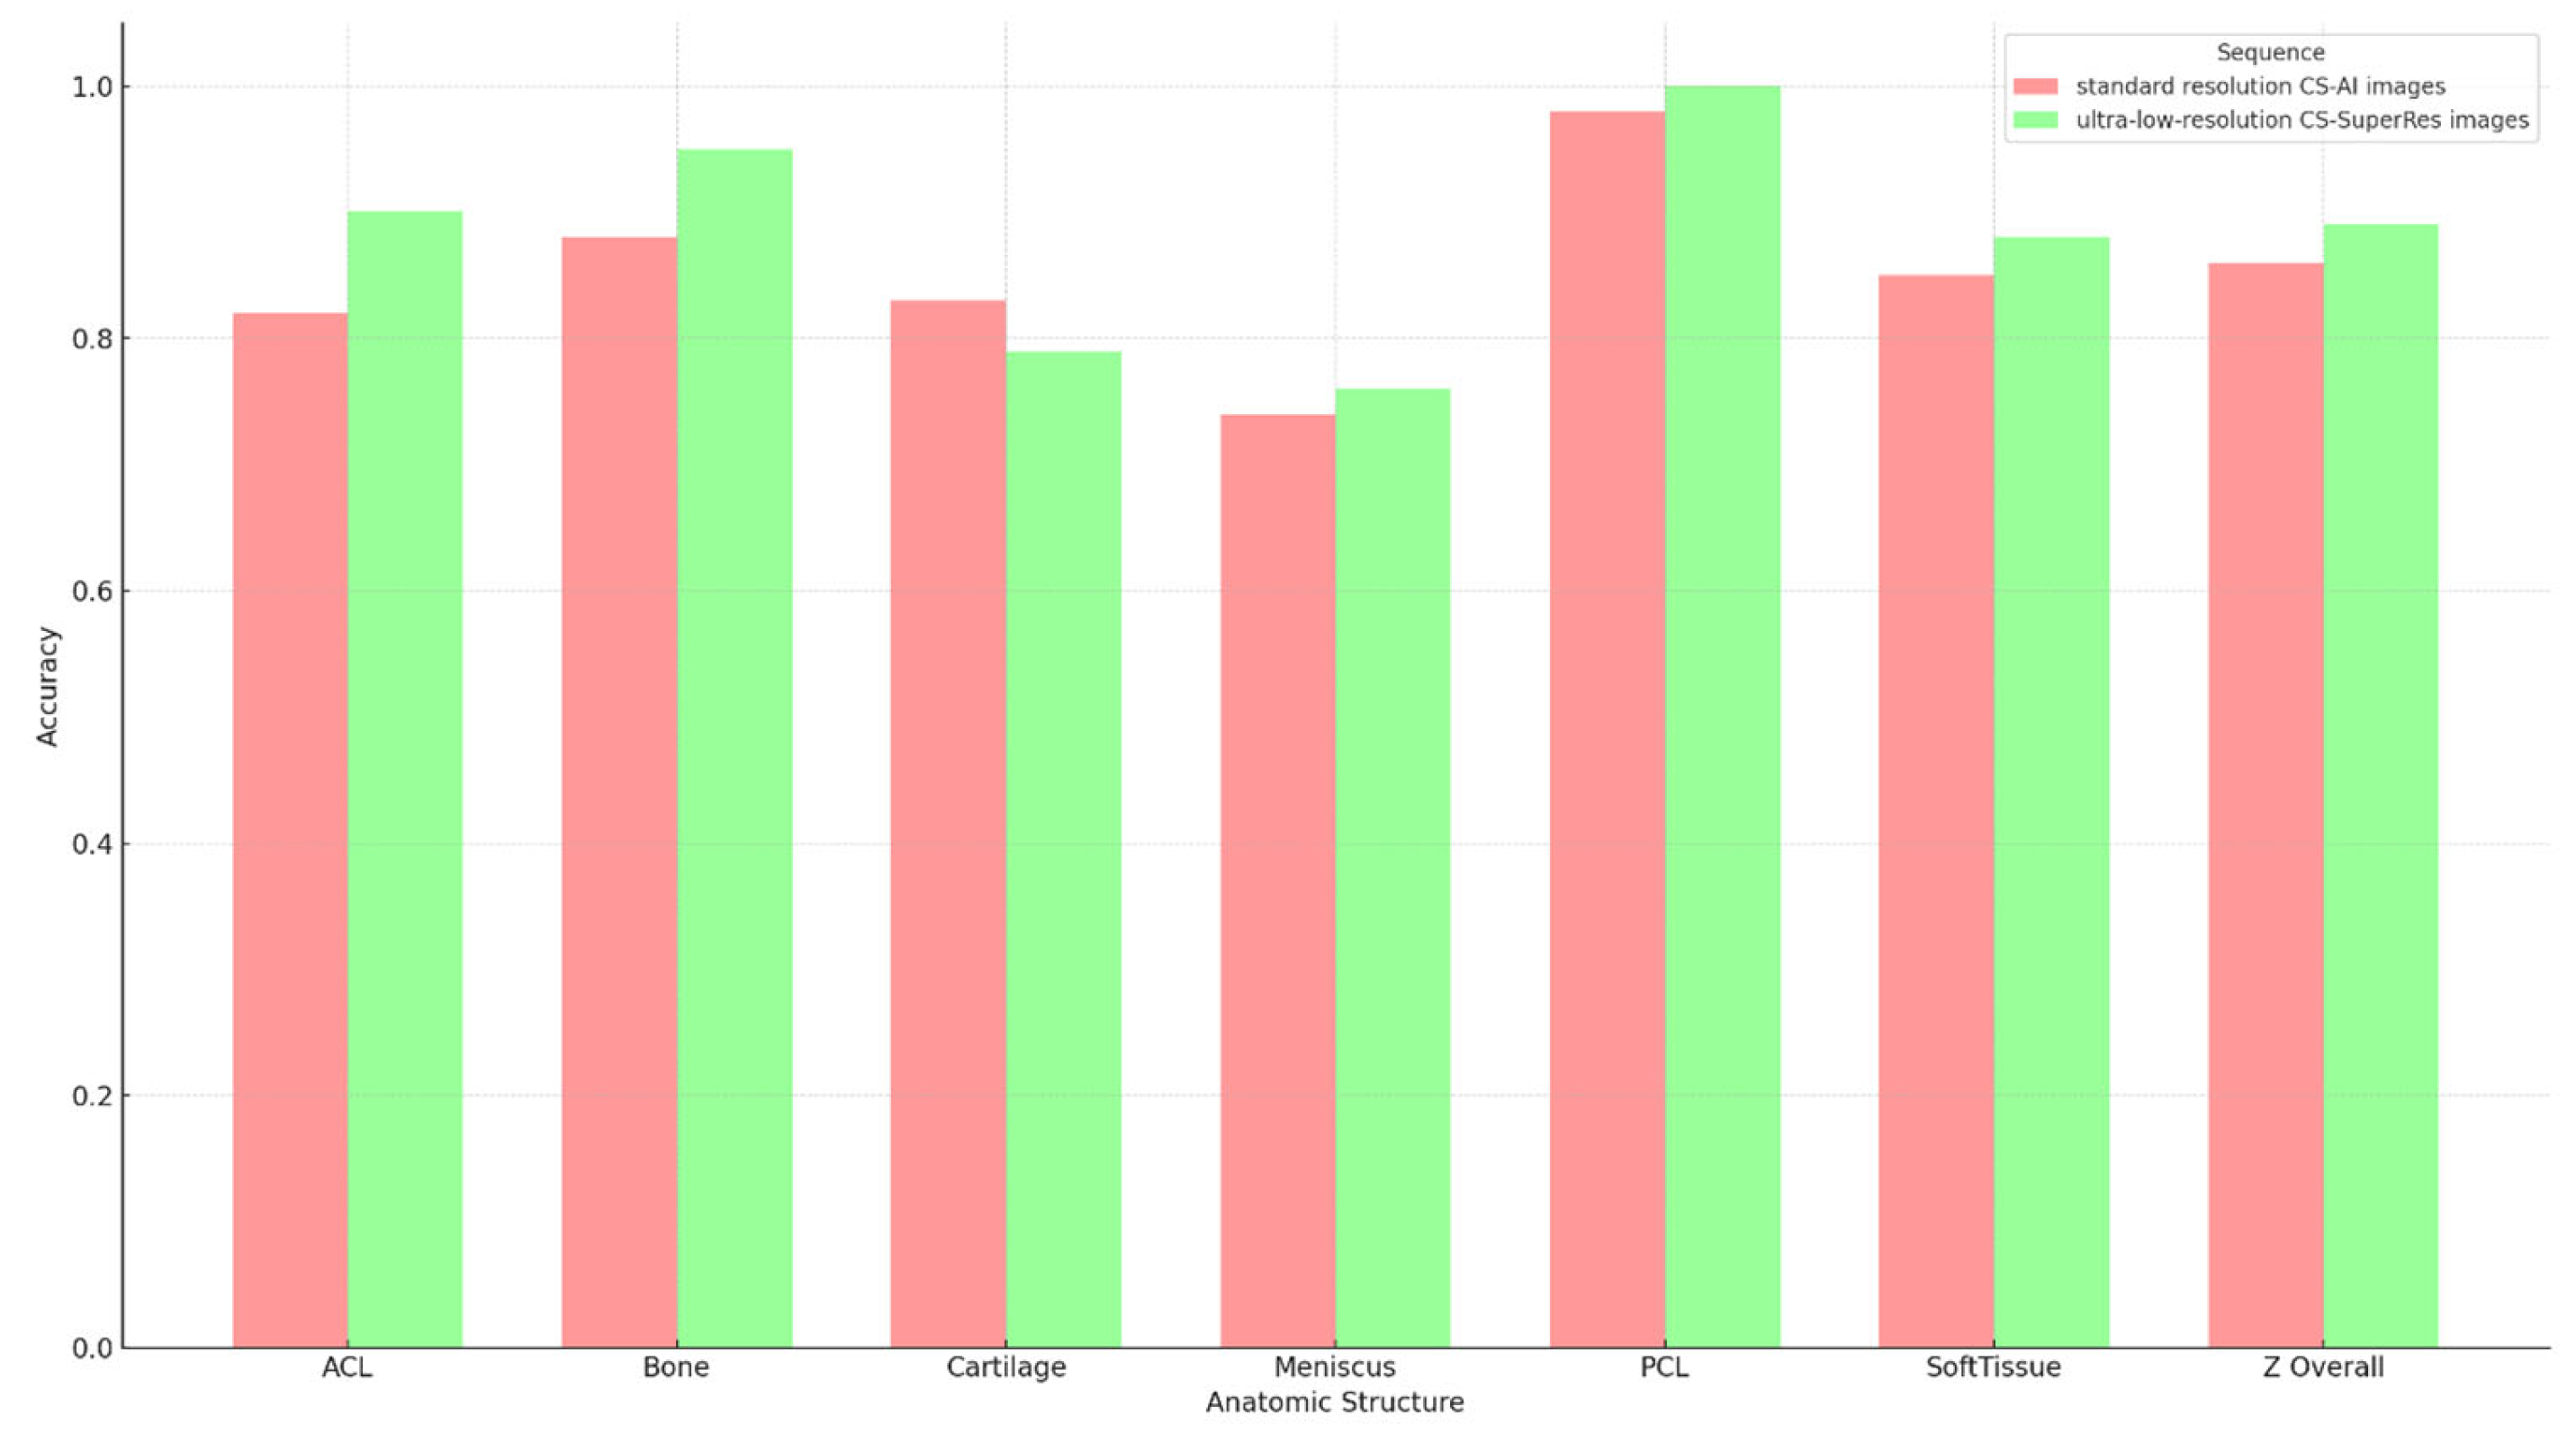

3.3. Subjective Image Analysis

| Anatomic Structure | Accuracy A | Sensitivity A | Specificity A | Accuracy B | Sensitivity B | Specificity B | p Value |

|---|---|---|---|---|---|---|---|

| ACL | 0.825 | NA | 0.825 | 0.9 | NA | 0.9 | 0.170 |

| Bone | 0.875 | 0.75 | 0.906 | 0.95 | 0.813 | 0.984 | 0.099 |

| Cartilage | 0.825 | 0.75 | 0.844 | 0.788 | 0.688 | 0.813 | 0.610 |

| Meniscus | 0.7375 | 0 | 0.776 | 0.763 | 0 | 0.803 | 0.702 |

| PCL | 0.975 | NA | 0.975 | 0.988 | NA | 0.988 | 0.563 |

| Soft Tissue | 0.838 | 0.5 | 0.855 | 0.863 | 0 | 0.908 | 0.431 |

| Overall | 0.846 | 0.65 | 0.864 | 0.875 | 0.6 | 0.9 | 0.130 |